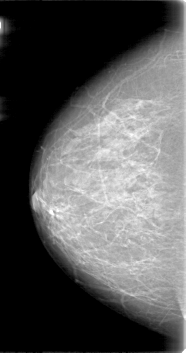

D_4019_1.RIGHT_CC

RIGHT_CC LINES 5281 PIXELS_PER_LINE 2776 BITS_PER_PIXEL 12 RESOLUTION 43.5 NON_OVERLAY